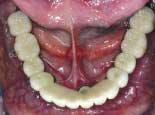

The fixed provisional restoration is placed in the mouth and screwed in place. The vertical dimension is confirmed and the occlusion adjusted. The screw holes are sealed with low viscosity polyvinyl impression material (figures 17 and 18).